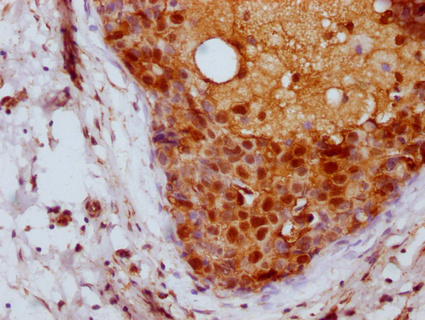

IHC image of CSB-PA04837A0Rb diluted at 1:100 and staining in paraffin-embedded human breast cancer performed on a Leica BondTM system. After dewaxing and hydration, antigen retrieval was mediated by high pressure in a citrate buffer (pH 6.0). Section was blocked with 10% normal goat serum 30min at RT. Then primary antibody (1% BSA) was incubated at 4°C overnight. The primary is detected by a Goat anti-rabbit IgG labeled by HRP and visualized using 0.05% DAB.